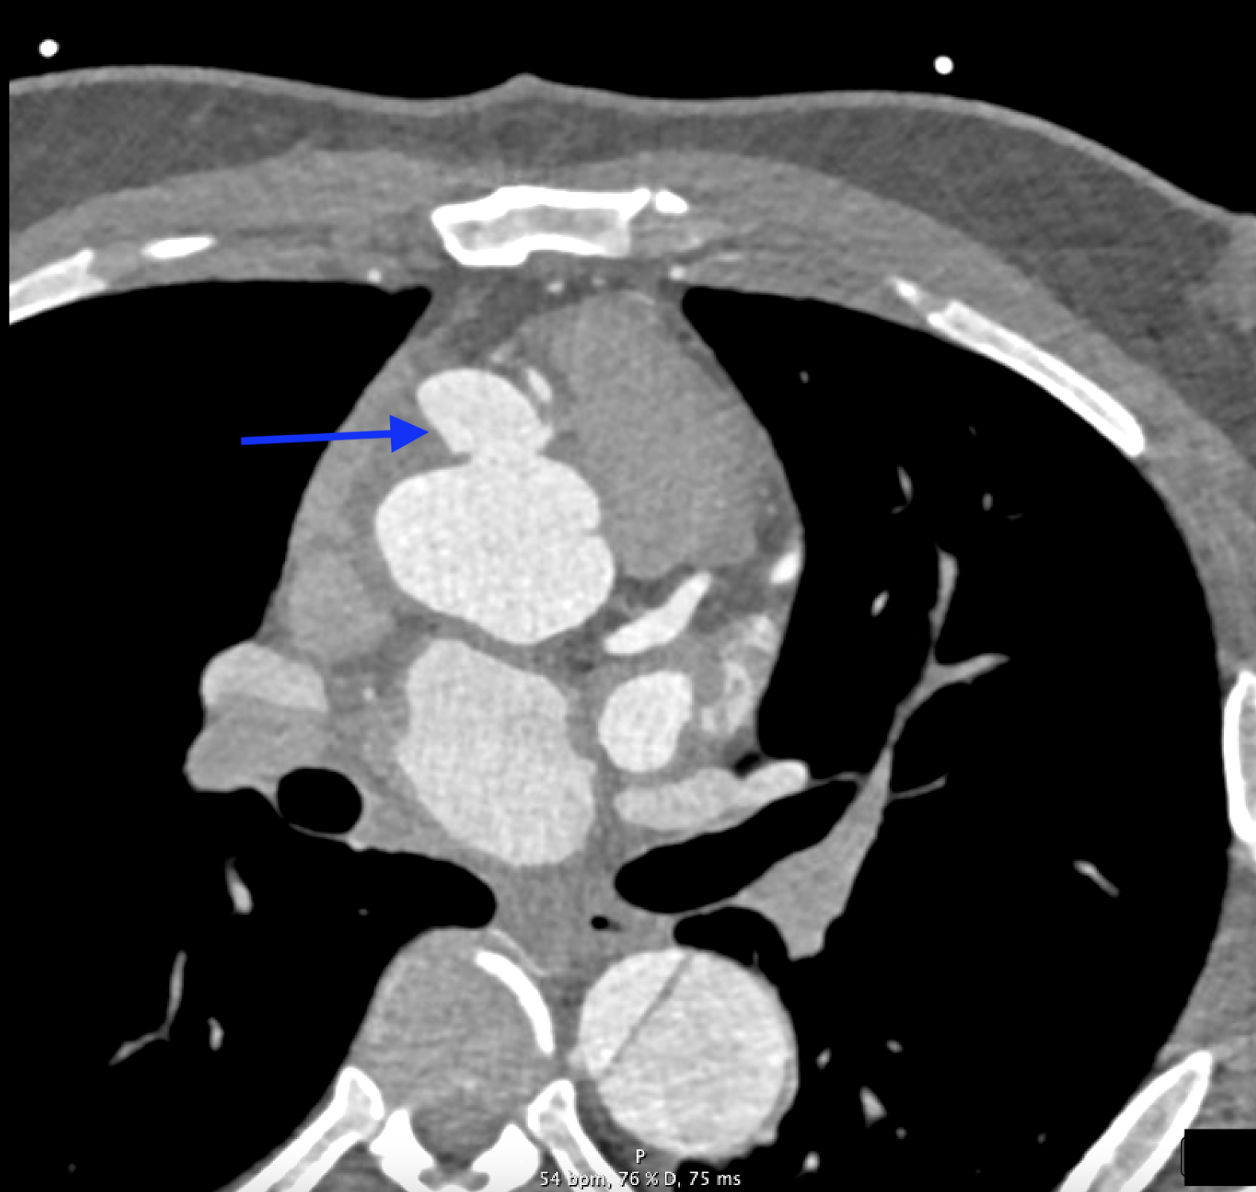

A 42-year-old male with history of a Type A aortic dissection with surgical repair 3 years earlier, resistant hypertension, hyperlipidemia, and prior tobacco use, presented for chest pain radiating to his back. Physical exam was notable for a 2/6 systolic murmur, most prominent at the aortic position. Initial vitals were significant for hypertension, with a blood pressure of 164/105 mmHg. Laboratory testing showed troponin elevated to 30 ng/L (reference < 15 ng/L), with a stable 3-hour trend. EKG showed normal sinus rhythm with left axis deviation and left ventricular hypertrophy. A CT angiography (CTA) dissection protocol showed a dissection flap distal to the left subclavian artery, extending into the abdominal aorta, consistent with a Stanford Type B aortic dissection (TBAD). The patient was managed with beta blockers and vasodilators to maintain systolic blood pressure under 120 mmHg and heart rate under 60 beats per minute. Following symptom resolution, a repeat thoracic CTA revealed a 2.5 cm sac near the origin of the right main coronary artery, representing a pseudoaneurysm not seen prior. Subsequent cardiac CTA confirmed this pseudoaneurysm outpouching secondary to degeneration of the TBAD. The patient underwent successful pseudoaneurysm repair with anastomosis construction and Dacron patch placement.

While the patient’s initial presentation and imaging studies, consistent with a TBAD, suggested conservative management, repeat imaging was imperative and changed the therapeutic plan despite the resolution of his symptoms. Current ACC/AHA guidelines recommend medical management for uncomplicated Type B dissections with close monitoring; however, aneurysmal progression mandates timely surgical intervention to mitigate rupture risk. This case highlights the importance of serial imaging in patients with TBADs to detect evolving complications such as APA formation, which may initially be occult but carry high mortality risk if left untreated.